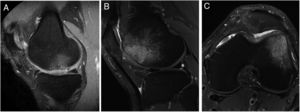

The presence of bone oedema was assessed by MRI in the 40 patients included in the study (Fig. 5). According to the study's inclusion/exclusion criteria, none of the patients had bone oedema on their baseline MRI. The MRI results showed very little variation in the number of patients who showed bone oedema at 6 months (9 patients), 12 months (10 patients) and 24 months (11 patients) following the HD-ACI high-density cell implantation. Likewise, no statistically significant differences were found when the 3 time periods were compared (p=.223). No statistically significant differences were found in the number of previous surgeries between the patients with or without oedema at 6 (p=.406), 12 (p=.701) and 24 months (p=.455) (median [minimum to maximum]: one previous surgery [0–5 surgeries] in the patients with oedema compared to previous surgery [0–4 surgeries] in the patients without oedema at 6, 12 and 24 months). There were no significant differences either in the number of lesions between the patients with and without oedema at 6 (p=.371), 12 (p=.233) and 24 months (p=.139) (one lesion [1–3 lesions]) in the patients with oedema as opposed to one lesion [1–3 lesions] in the patients without oedema in the 3 follow-up times). Finally, no significant differences were found in the size of the lesions among the patients with or without oedema at 6 (p=.503), 12 (p=.939) and 24 months (p=.720) (4cm2 [1.2–10.5cm2] in the patients with oedema compared to 4.6cm2 [1.5–8cm2] in the patients without oedema at 6, 12, and 24 months).

Representative MR images showing the appearance of subcondral bone oedema in 2 patients at 12 months (A) and 24 months (B and C) following high-density autologous chondrocyte implantation (HD-ACI). A) Subchondral oedema in the weight-bearing area of the internal femoral condyle, with intact meniscus and irregularity in subchondral bone (sagittal slice). Sagittal slice (B) and axial slice (C) of MRI of a patient with bone oedema in the external femoral condyle (trochlea) showing good integration of the chondrocyte implant with the subchondral bone.

In order to study whether there was a relationship between the presence of bone oedema and the patients’ clinical outcomes, the IKDC scores were compared between the patients who presented bone oedema and those who did not, at 12 and 24 months following treatment with HD-ACI (Table 2). We found no significant differences between the 2 groups in any of the follow-up periods (p=.933 at 12 months; p=.919 at 20 months). Likewise, there was no correlation with the presence of bone oedema and the mean difference in IKDC scores at 12 months (p=.959; Spearman's correlation coefficient=−.009) and 24 months (p=.867; Spearman's correlation coefficient=−.029) compared to the baseline visit. We observed in all the patients included in the study that the area of the implant on the follow-up MRI scans showed a homogeneous and continuous signal, compatible with correct integration of the implant in all cases.